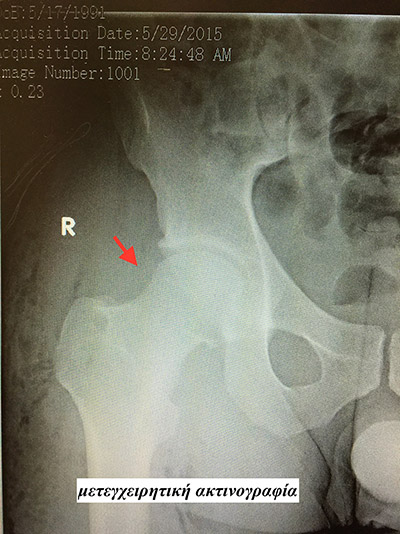

Η έγκαιρη αρθροσκοπική αντιμετώπιση της μηροκοτυλιαίας πρόσκρουσης αποτελεί τη συχνότερη ένδειξη αρθροσκόπησης του ισχίου και επιτρέπει στους ασθενείς να απαλλαγούν από τον πόνο του ισχίου και να επειστρέψουν σύντομα στις καθημερινές τους δραστηριότες και την εργασία τους αναστέλλοντας παράλληλα την εξέλιξη προς την οστεοαρθρίτιδα.

Η αρχόμενη οστεοαρθρίτιδα του ισχίου είναι μια άλλη ένδειξη της αρθροσκόπησης του ισχίου. Μεγάλο πλεονέκτημα της τεχνικής είναι η αναίμακτη, ανώδυνη προσέγγιση της άρθρωσης, η διατήρηση της ανατομίας της άρθρωσης και η γρήγορη επάνοδος στην καθημερινότητα. Η αρθροσκόπηση ισχίου δεν απαιτεί νοσηλεία, ο ασθενής δύναται να αυτοεξυπηρετείται άμεσα ενώ η έγκαιρη αντιμετώπιση οδηγεί στο καλύτερο αποτέλεσμα.

Η αρθροσκόπηση του ισχίου εξελίσσεται με γοργούς ρυθμούς τα τελευταία 5 χρόνια και στη χώρα μας. Στο Θεραπευτήριο ΜΕΤΡΟΠΟΛΙΤΑΝ με τα πλέον εξελιγμένα ιατρικά εργαλεία, το εξειδικευμένο και έμπειρο ιατρικό και νοσηλευτικό προσωπικό οι ασθενείς απολαμβάνουν τα οφέλη της εξέλιξης αυτής, με την πρώιμη αναγνώριση παθολογικών καταστάσεων και τη λιγότερο παρεμβατική αντιμετώπιση αυτών. (εικόνα 7)